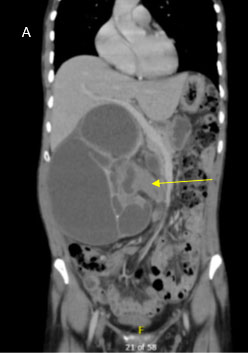

A 58-year-old woman with a past medical history notable for hypothyroidism presented for evaluation in March 2021, after incidental diagnosis of a 1.3 cm left renal mass on imaging obtained for workup of right upper quadrant abdominal pain in 2020. Comparison of her initial scan from 2020 to her more recent cross-sectional imaging showed an approximately 1.4 cm left lower pole partially exophytic lesion measuring 35 HU on noncontrasted phase with slight enhancement to 58 HU on the nephrogenic phase, which was overall stable in size (Figure 1). Staging imaging with chest X-ray did not demonstrate any evidence of metastatic disease and she had no systemic symptoms related to the mass. After a discussion of the options for management, including active surveillance, cryoablation, or partial nephrectomy, she initially elected for active surveillance. This lesion was monitored with minimal change in size or characteristics on serial computed tomography (CT) abdominal scans with and without contrast every six months until May 2022, at which point she elected to proceed with partial nephrectomy. Her imaging did not indicate growth over this 18 month period.

Figure 1: Abdominal CT imaging of MA. (A) Noncontrast phase CT measuring 35 HU, (B) Contrasted phase CT with slight enhancement to 58 HU on the nephrogenic phase.